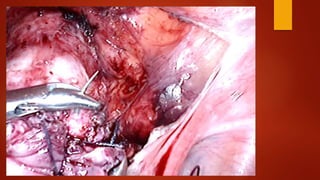

Суть метода После вскрытияпузырно-маточной складки брюшины и низведения мочевого пузыря при помощи монополярного электрода типа «Игла» рассекается рубец.

Края рубца «освежевываются»с помощью ножниц без использования энергий. Далее стенки матки ушиваются синтетической рассасывающейся нитью «Викрил» №1 отдельными швами в два ряда. Перитонизация.